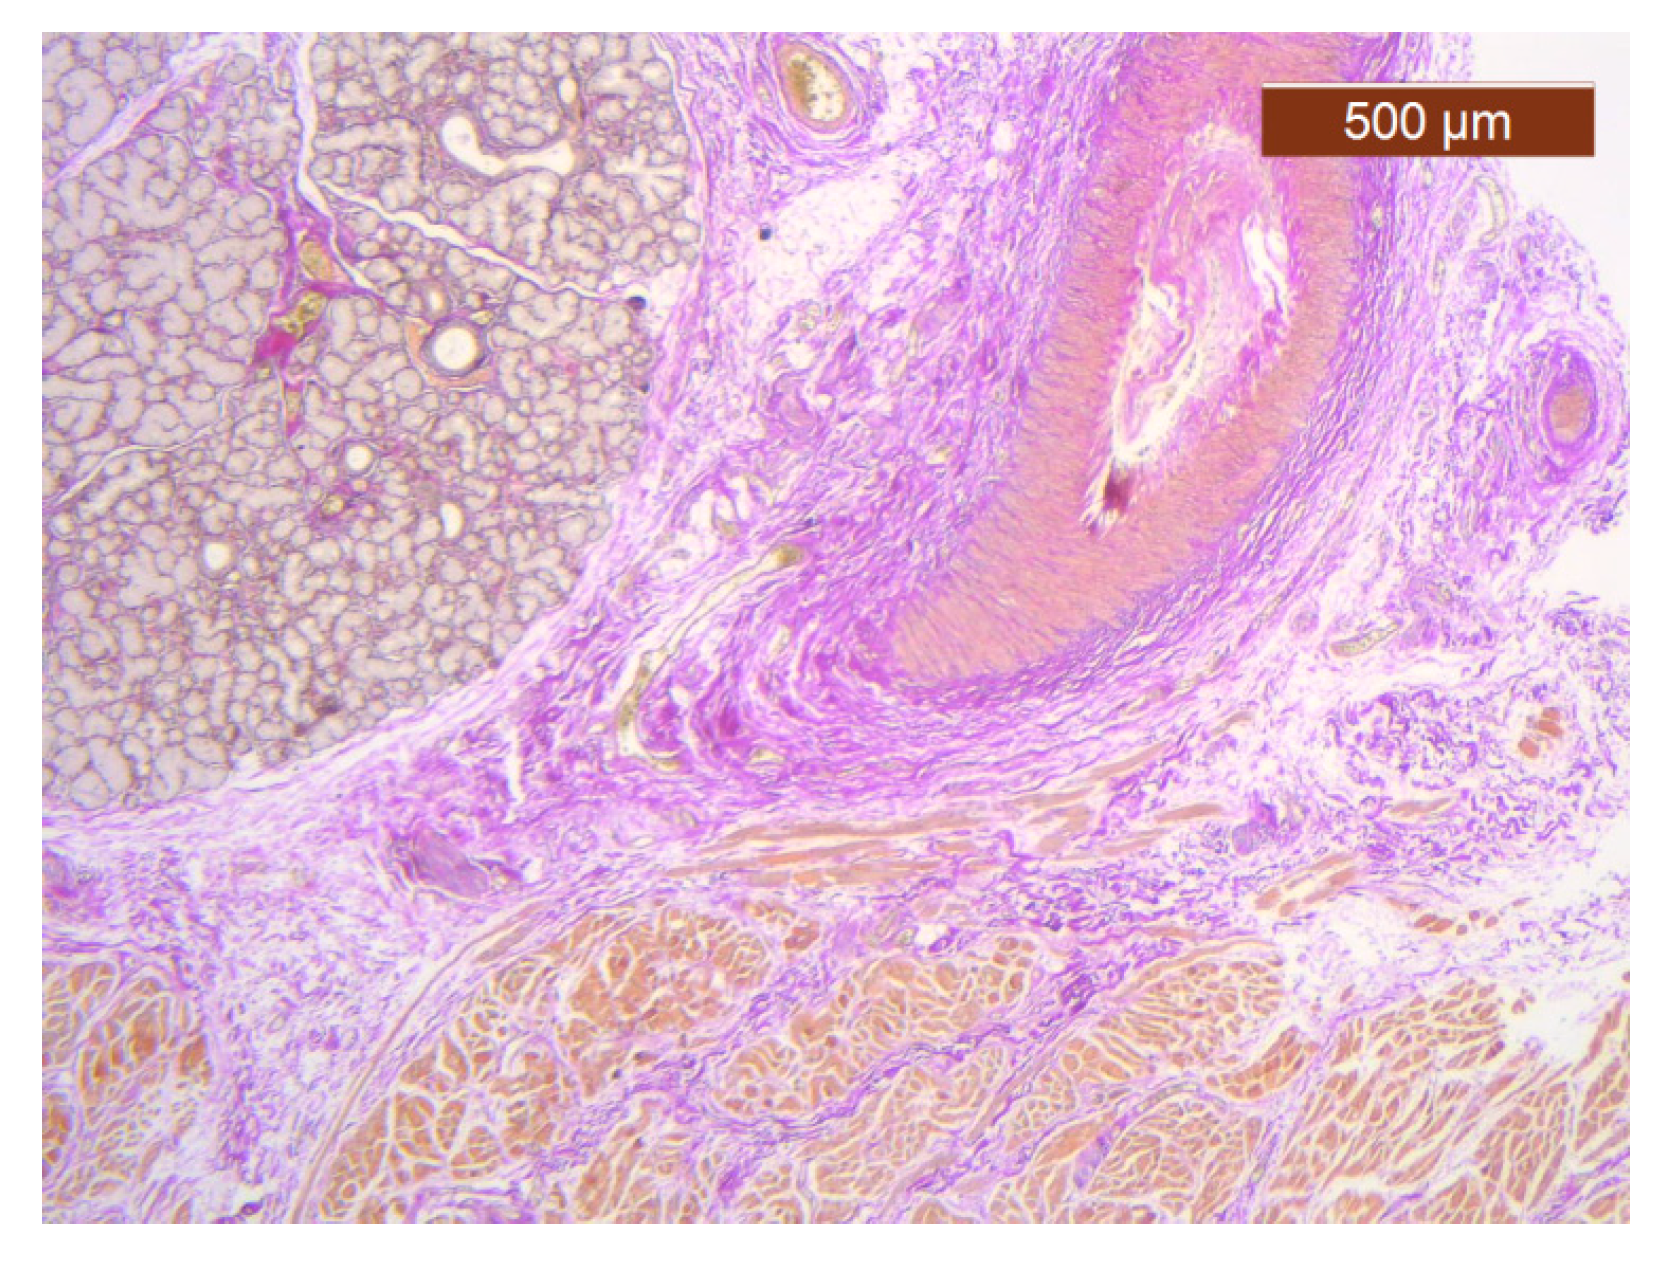

Figure 10. Subcutaneous collagen thick septa. Collagen fibers (deep), blood vessels, and fat cells (middle alar area) (HE ×5).

In this region, the arrangement of the SMAS layers from the superficial to the deep layers seemed very particular. Thus, in the immediate infradermal layer, we found strong collagen septa (Figure 10). The representation of blood vessels and muscle tissue at this level was almost absent.

Immediately below this layer follows an intermediate layer in which fat lobules are surrounded by collagen III fibers, with an apparently irregular arrangement, and blood vessels (Figure 11, Figure 12 and Figure 13). The muscle tissue is also present in this intermediate layer, but it was poorly represented (Figure 14).